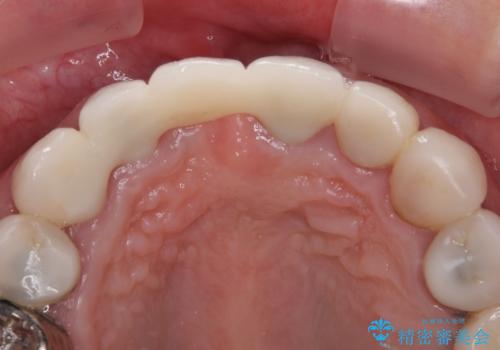

元々の土台は歯肉の中に埋もれており、歯肉が著しく腫れている状態だったため、歯を引っぱり出すこととしました。引っぱる期間は2ヶ月ほどで済み、その後歯周外科処置を行ったことで、土台周りの歯肉は腫脹のない健全な状態へと改善されました。